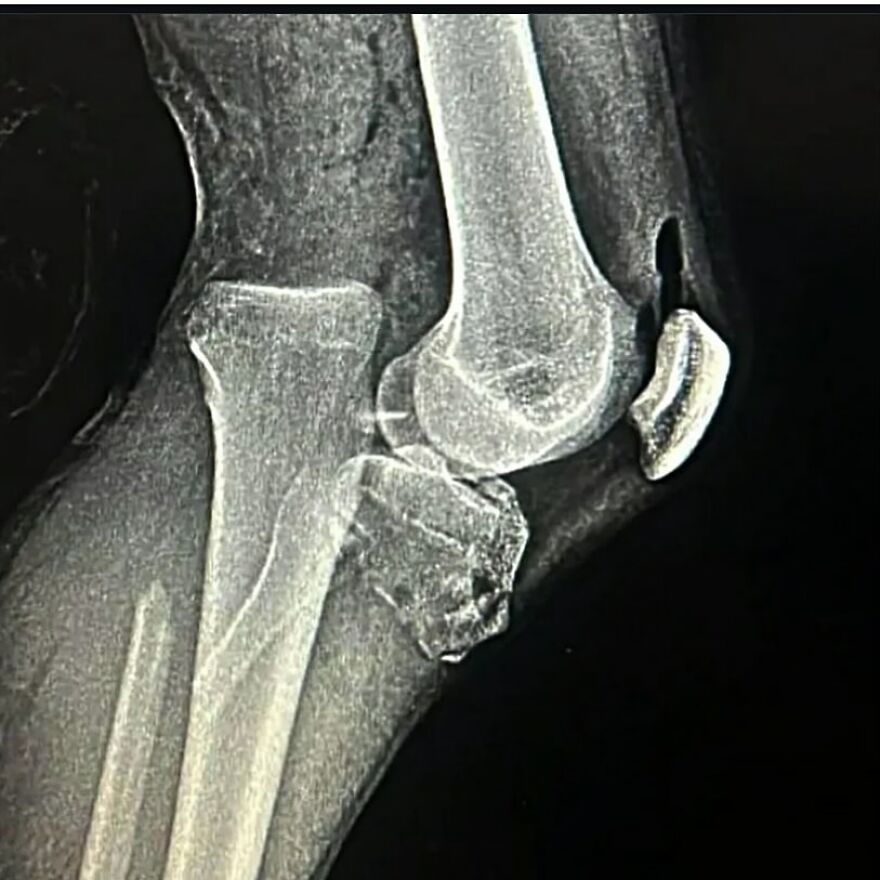

A dodgeball injury that resulted in radius and ulnar shaft fracture, aka broken forearm!

This sustained dodgeball injury has led to a bilateral diaphyseal fracture involving both the radius and ulnar shaft, thereby presenting as a fracture of the forearm.

This particular injury entails the disruptive discontinuity of the long bones situated within the antebrachial region, namely the radius and ulnar diaphyses.